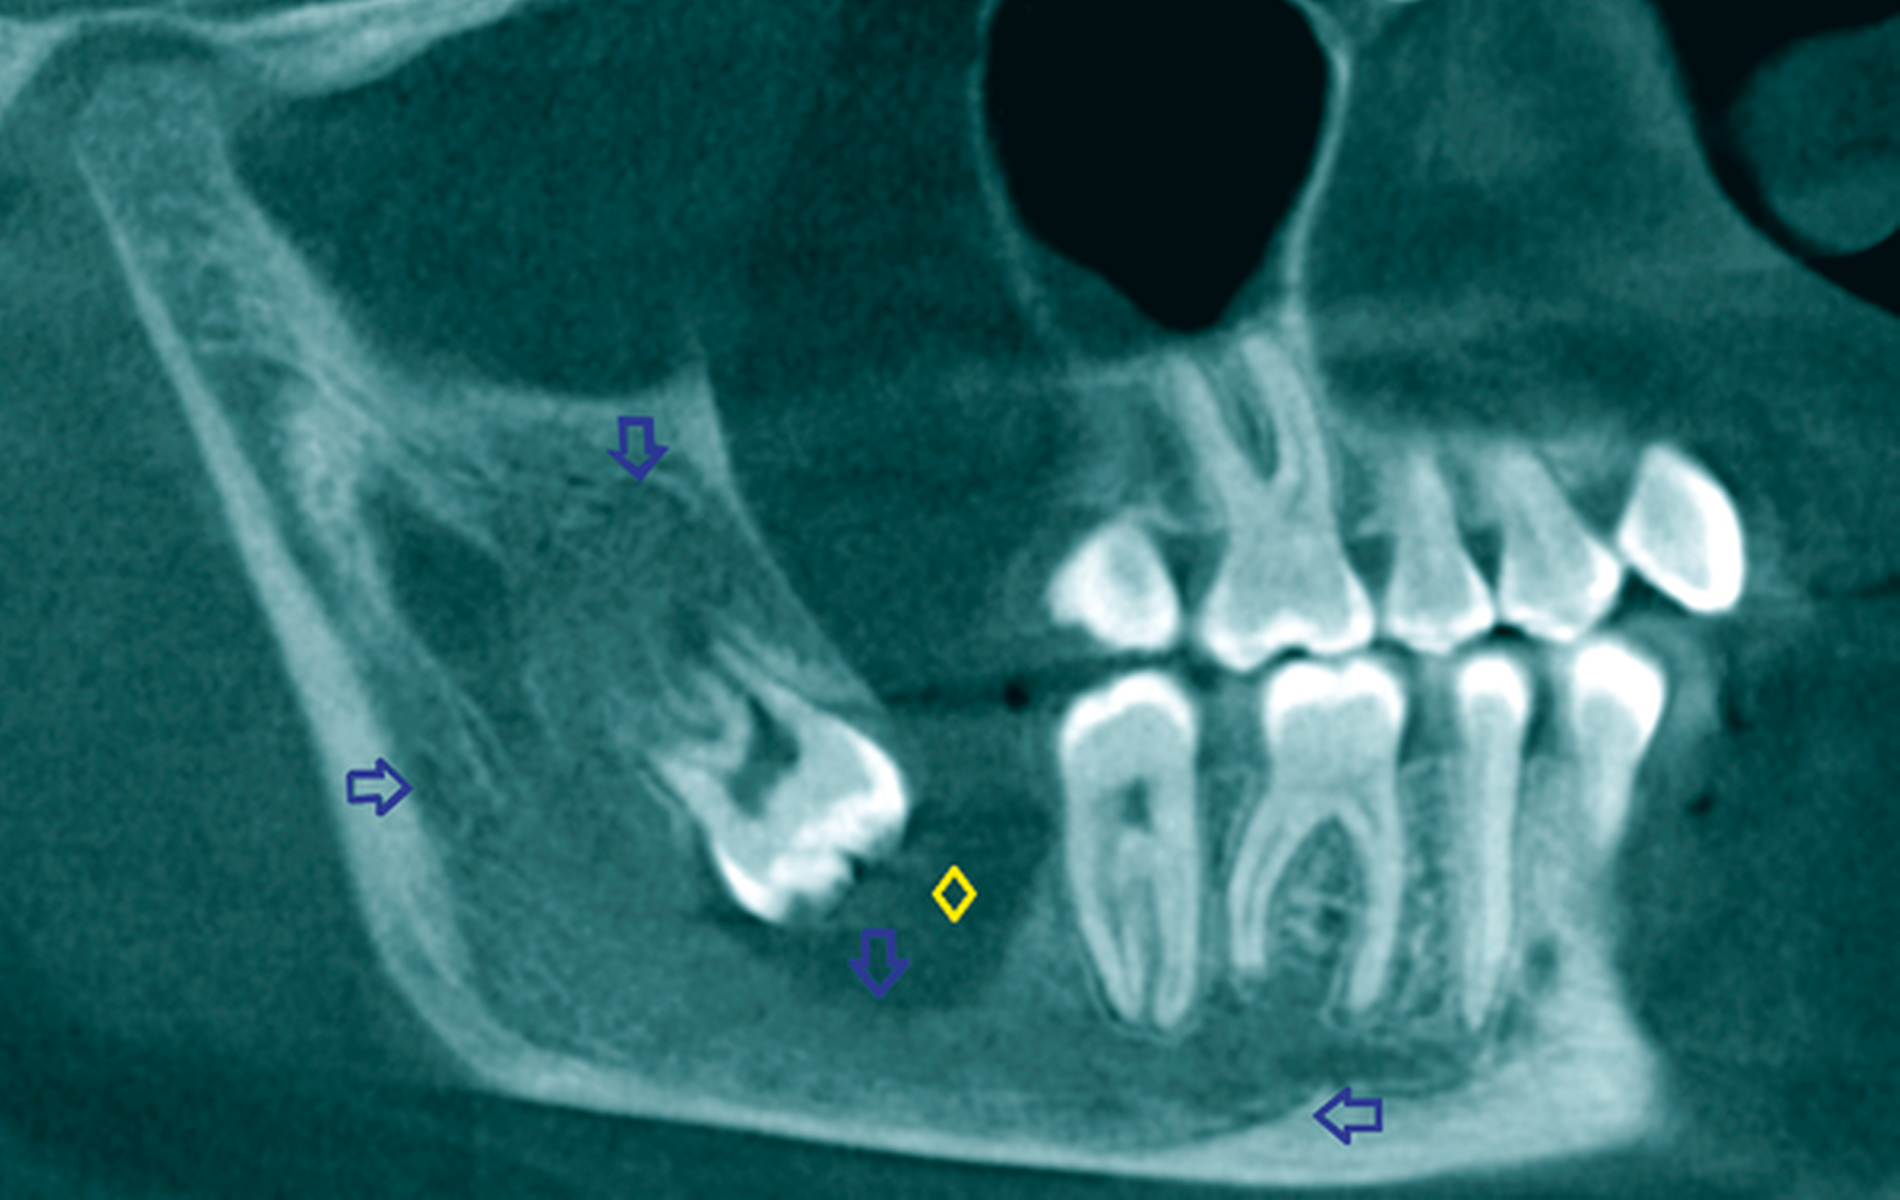

Ein 52-jähriger Patient stellte sich mit Überweisung und Bitte um Therapie einer zystischen Raumforderung im Bereich des rechten Kieferwinkels über unser MVZ vor (Abbildung 6a). Aufgrund der erhöhten Frakturgefahr bei einem weit nach kaudal verlagerten Zahn 48 entschied sich der Patient nach entsprechender Aufklärung für das mehrzeitige Verfahren mittels Zystostomie. Die Versorgung erfolgte in diesem Fall mit einem nicht zahngetragenen Obturator, der lediglich mittels eines Gingivaschildes ins Vestibulum eingelagert war. Der Patient kam damit nach initialer individueller Einpassung gut zurecht. Die radiologischen Kontrollen erfolgten nach histologischer Sicherung einer follikulären Zyste halbjährlich zur Sicherung des Therapieerfolgs. Bei nach elf Monaten deutlich regredientem Befund konnte die Zystektomie und operative Entfernung des Zahnes 48 in ambulanter Allgemeinanästhesie durchgeführt werden, wobei keine perioperativen Komplikationen auftraten (Abbildung 6b). Besonders hervorzuheben ist die Wanderungsbewegung des Zahnes 48 nach koronal. Abbildung 6c zeigt die knöcherne Konsolidierung des Defekts sieben Monate postoperativ bei Beschwerdefreiheit. Bezüglich des vitalen Zahns 47 (ohne Lockerung) wurde eine prothetische Versorgung durch den Hauszahnarzt empfohlen.